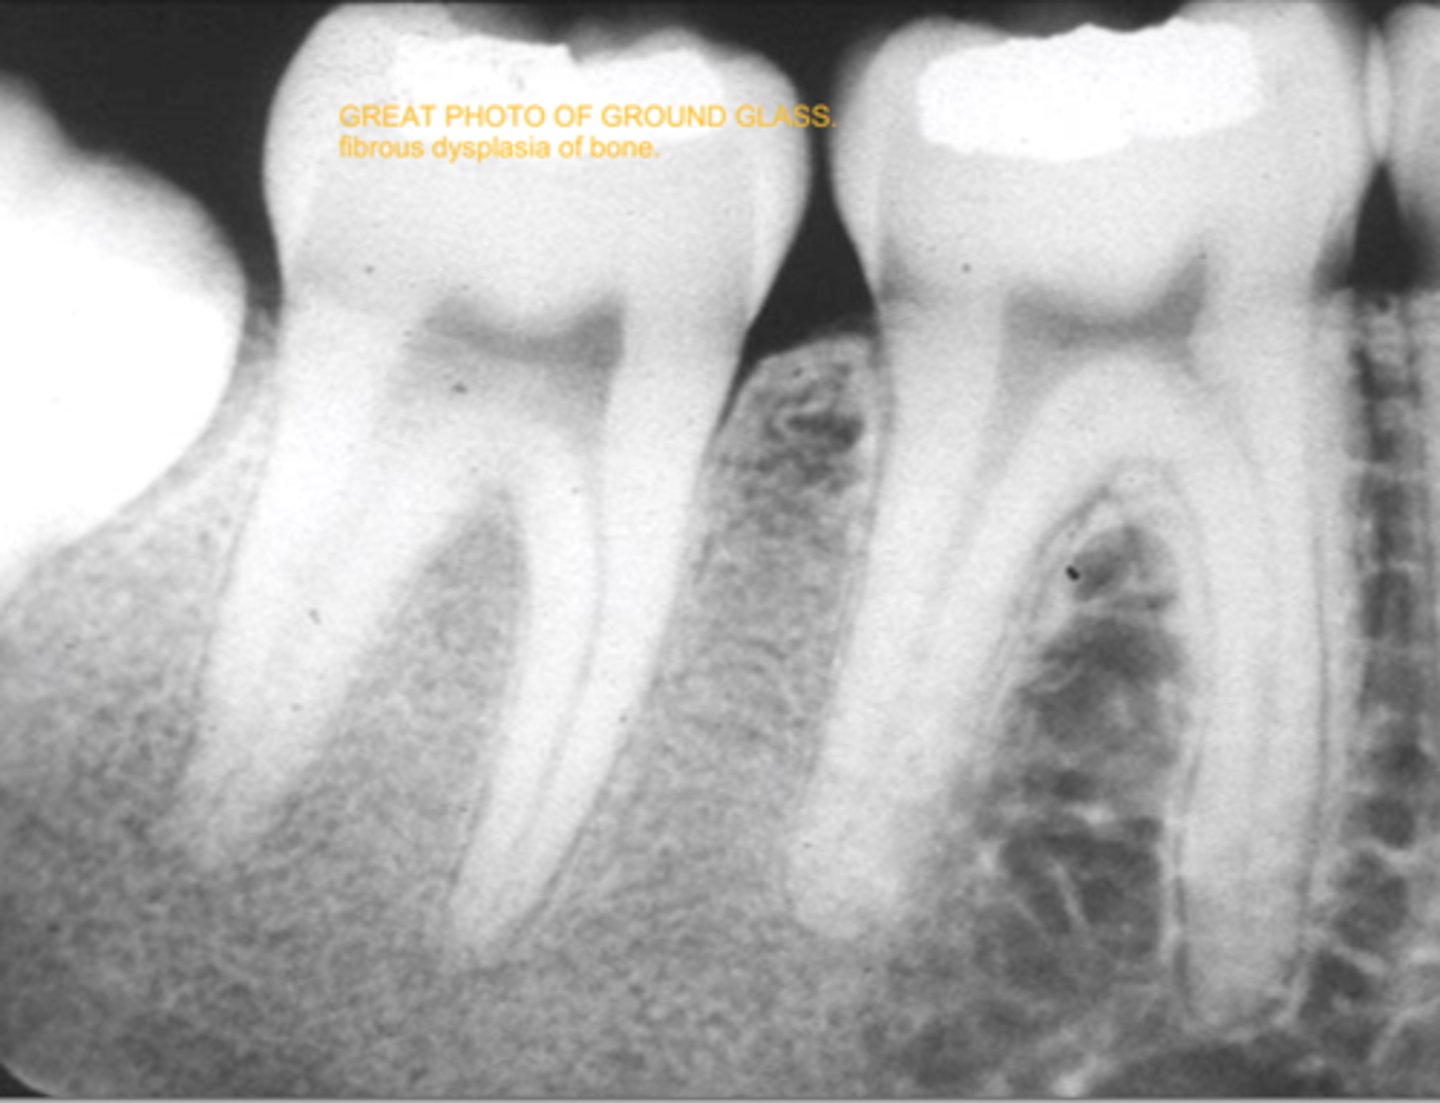

what is fibrous dysplasia

it is an uncommon chronic benign bone disease where bone is replaced w CT; it is usually monostotic but it may be polyostotic

fibrous dysplasia

cause: unknown

clinical features: painless gradual enlargment of bone replaced by fibrous CT (paget's is gradual enlargement presenting w pain)

oral features: maxilla is affected (like paget's); bone expansion/displacement

radiographic: ground glass/orange peel appearance

prognosis: guarded bc of 25-50% recurrence

population: teens/YA <20s